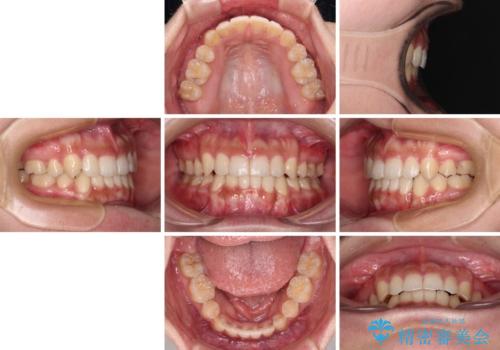

ワイヤー装置を用いた場合、一般的には2年程度で終了することを考えると、「移動量が多くなると治療期間が長くなる」というインビザライン矯正の最大の弱点が現れた治療となりました。